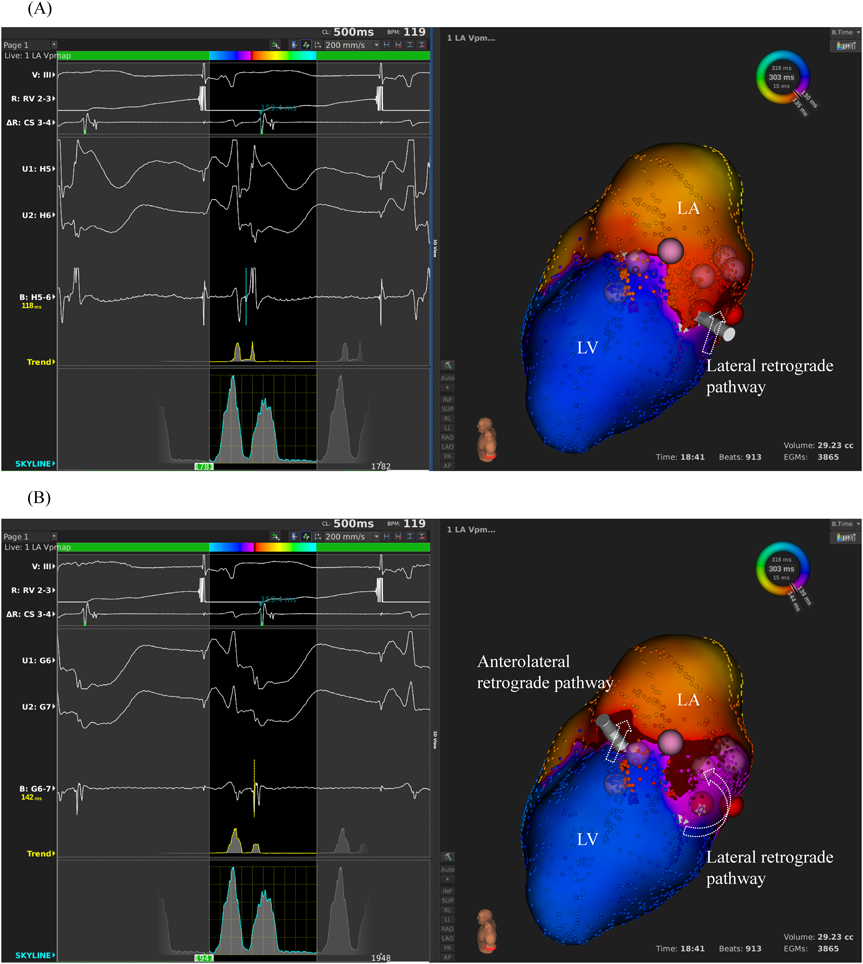

We used intracardiac echocardiography and a radiofrequency needle to perform transseptal puncture, and then inserted a long deflectable sheath (C MAP SYMMETRY; Century Medical, Inc. Tokyo, Japan) into the left atrium. During right ventricular pacing, we used the ORION™ high-density catheter (Boston Scientific) and the RHYTHMIA™ Mapping System to perform activation mapping, which demonstrated early left lateral activation followed by anterolateral atrial activation. Anterolateral activation, however, sometimes occurred as early as left lateral activation (Fig. 2A, 2B). The propagated waves collided at the distal portion of the left atrium through the mitral annulus. On activation mapping, the earliest atrial activation during AVRT coincided with that during right ventricular pacing (Fig. 3A, 3B; Supplementary Movie). Furthermore, 3D mapping showed that these earliest sites of atrial activation were 16.7 mm apart.

Fig. 2 (A) Activation mapping during right ventricular pacing. Left panel: the intracardiac electrocardiogram of the earliest atrial activation at the left lateral part. Right panel: the activation map, in which the tip of the catheter is positioned at the left lateral accessory pathway. The arrow indicates the lateral retrograde pathway. (B) Left panel: the intracardiac electrocardiogram of left anterolateral atrial activation, which sometimes occurred as early as left lateral atrial activation. Right panel: the activation map, in which the tip of the catheter is positioned at the left anterolateral accessory pathway. The red and pink dots reflect radiofrequency application for the lateral and the anterolateral accessory pathways, respectively. The straight arrow indicates the anterolateral retrograde pathway; the curved arrow indicates the lateral retrograde pathway.

LA, left atrium; LV, left ventricle.